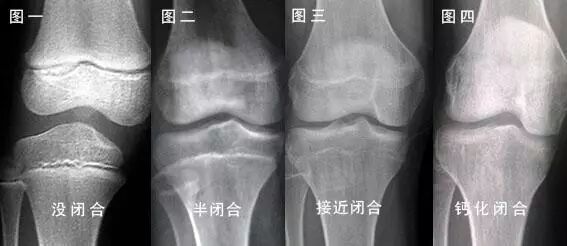

当孩子进入青春期以后,生长加快,骨龄也相应的迅速增大,切不可等到发育后期如15~18岁时再治疗,此时骨骺接近闭合,生长潜力很小,已不再可能达到理想身高。而随着骨骺闭合,再进行治疗,将无生长空间,造成终身遗憾。

4.什么是骨骺线?